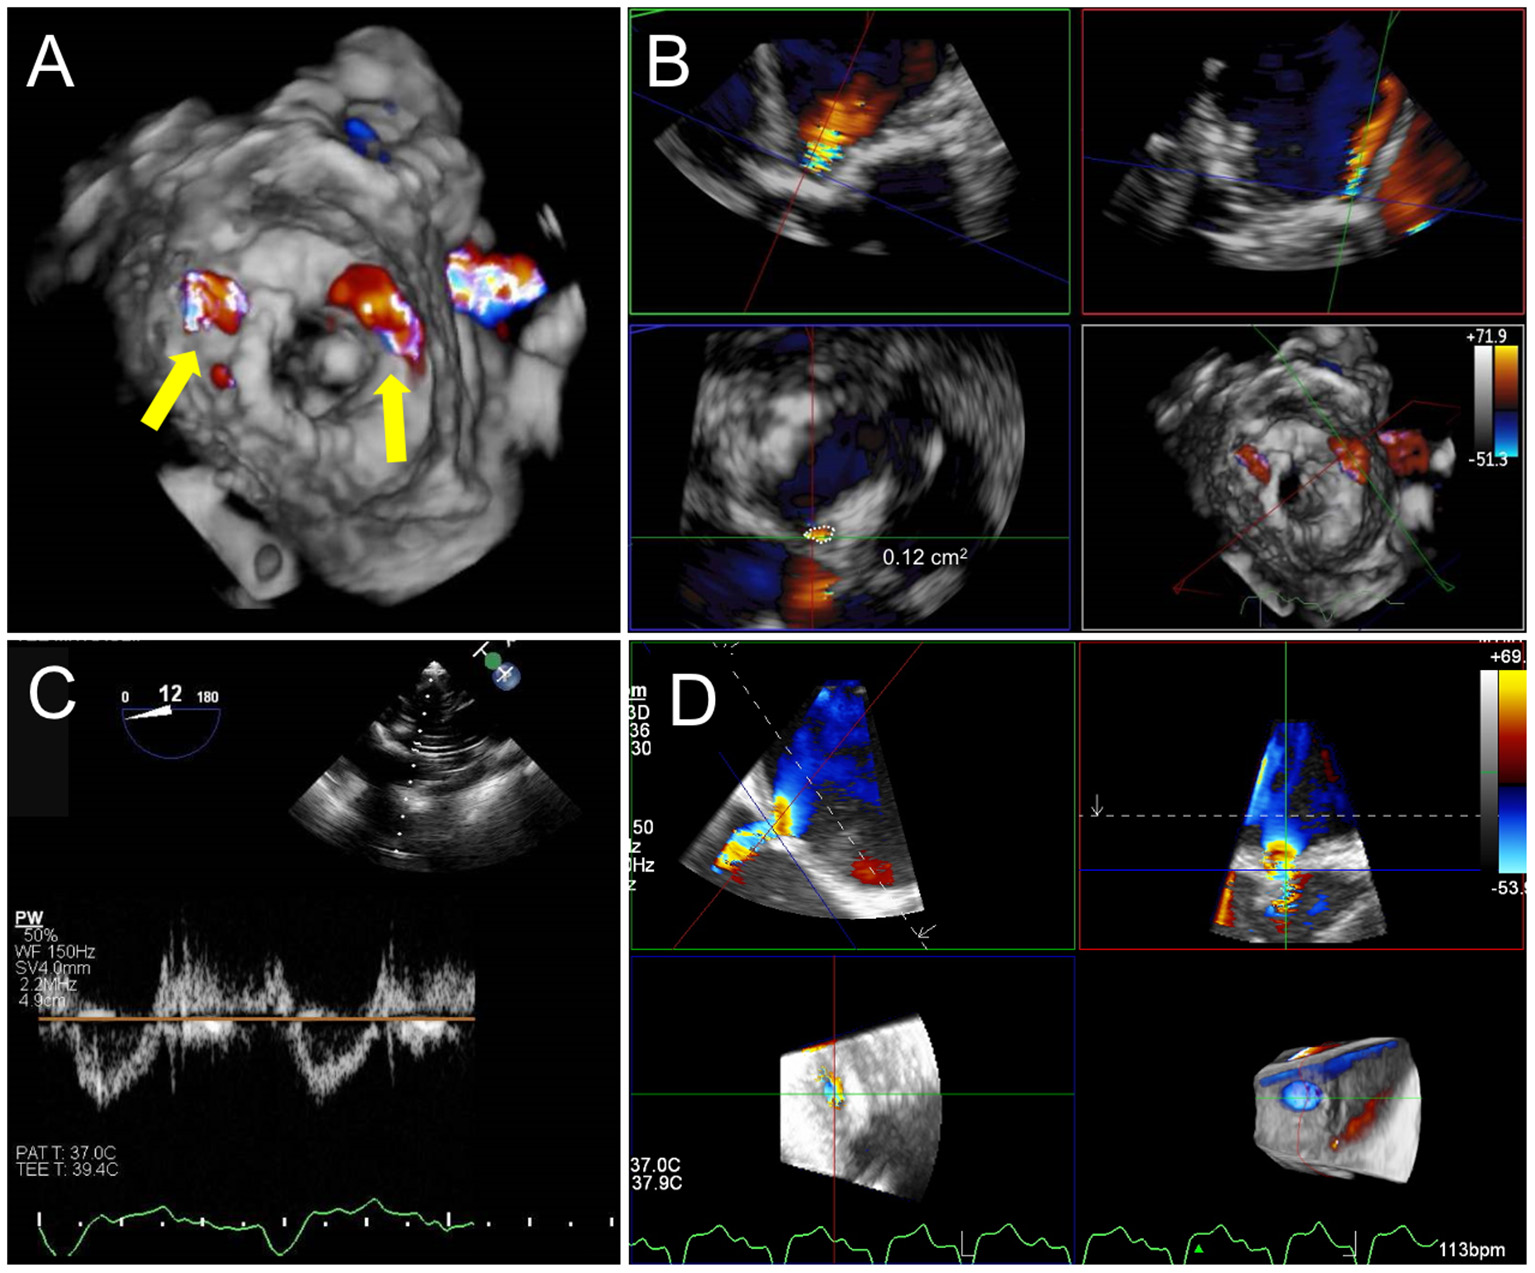

Figure 10

Post TMVR assessment immediately after deployment. (A) 3D color Doppler evaluation from an en-face surgeon's view immediately after a valve in MAC implantation reveals two areas of paravalvular leak (PVL) at 10 and 1 o'clock (yellow arrows). See Supplementary Video 3 for 3D en face evaluation of valve morphology and leaflet motion. (B) Careful interrogation of the largest area of PVL with 3D MPR reveals a vena contracta area of 0.12 cm2. (C) Pulsed-wave Doppler interrogation of the LVOT from a transgastric view in order to exclude a significant gradient or obstruction. (D) Evaluation of residual iatrogenic septal defect size and direction of flow.

Given the significant risk for LVOTo, particularly with a valve in a native annulus, it is imperative to carefully assess LVOT flow and gradients after device deployment. In addition to a mid-esophageal long-axis view for color Doppler assessment, evaluation of LVOT gradients is best achieved by PW Doppler interrogation from a deep trans-gastric view. MPR of a high-quality 3D TEE dataset can be utilized to measure the resultant neo-LVOT area. However, acoustic shadowing is a limitation of TEE visualization, and there may be a role for TEE-CT fusion for neo-LVOT assessment (52).

Finally, after device deployment and following removal of the delivery system and sheath, attention should be paid to the interatrial septum to identify and assess the iatrogenic atrial septal defect (iASD) and direction of flow. Though many of these defects resolve spontaneously and are without clinical consequences, persistent iASD at 6 months has been associated with adverse outcomes after transcatheter mitral valve repair (53). The immediate closure of iASD may be necessary if hypoxia and a right-to-left shunt are noted or if the defect is very large.